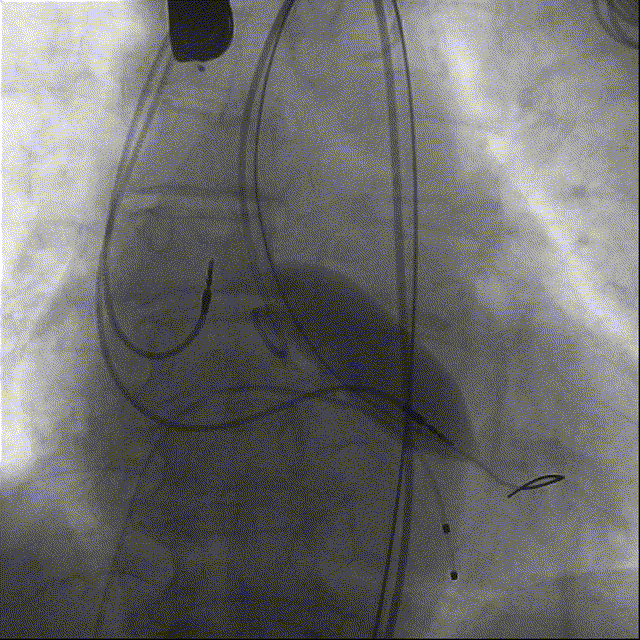

瓣膜初始定位

第一次释放过程